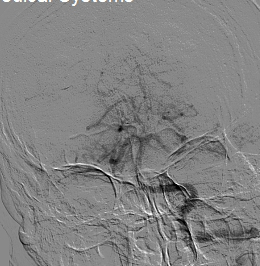

选择4.0×20mm支架,采用swim技术取栓2次,取出少量暗红色血栓,颈动脉造影未见血流恢复,单支架取栓无效。

考虑血栓负荷量大,遂采用双支架取栓技术。

该病例为颈内动脉C1段远端闭塞,血栓负荷率大,我们采用常规的SWIM技术(支架取栓+抽栓),但是效果不佳,于是改为双支架串联技术取栓,达到mTICI 2b级血管再通效果。

针对本例患者,选择了单纯使用导引导管的双支架串联式释放同时局部并联释放技术,双重支架叠加可以增加支架释放的径向支撑力,同时也增加了支架网丝对血栓的嵌入效应、接触面积和血栓的缠绕能力,快速将血栓拉出体外,提高了开通效率,并最终获得良好开通效果和3个月良好预后。